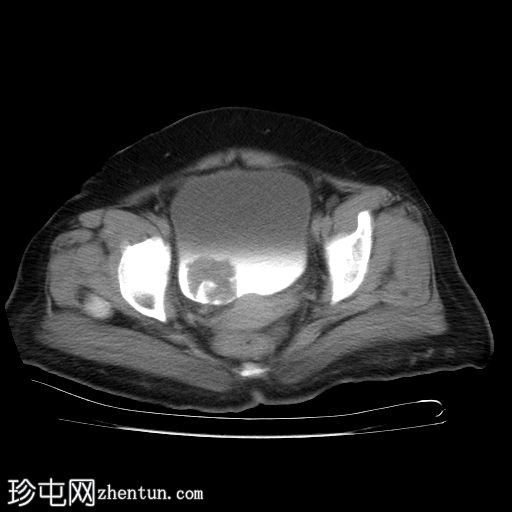

静脉注射造影剂轴位

增强扫描

2.jpg

膀胱内可见一边界清晰、不规则、可移动的软组织病变(CT值65 HU),直径约40 mm。病变无钙化,增强扫描后无强化。首要鉴别诊断为血肿。